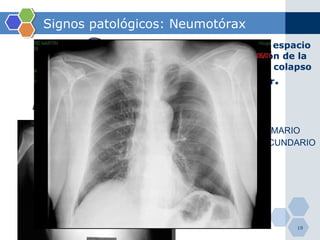

Signos patológicos: Neumotórax Entrada de aire en espacio pleural, disminución de la presión negativa y colapso pulmonar posterior . ESPONTÁNEO PRIMARIO ESPONTÁNEO SECUNDARIO TRAUMÁTICO YATROGÉNICO CATAMENIAL